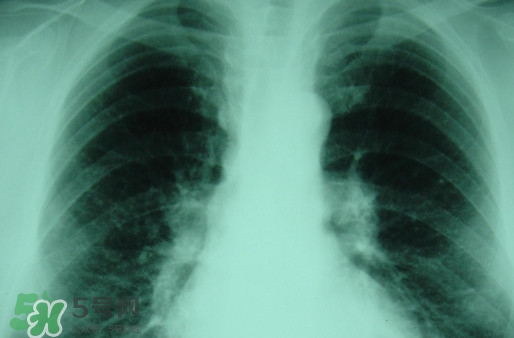

對于塵肺病,很多人都是陌生而又熟悉,因為其就是一種人體肺部滿身灰塵的病癥,一般從事煤礦或是珠寶打磨行業(yè)人群患病率高。那么,塵肺病能治愈嗎?塵肺病能活多久?

塵肺病受制于現(xiàn)行的醫(yī)療技術,目前塵肺病是無法徹底治好的。

輕微患者可以考慮洗肺,重癥患者建議采取保守治療。

塵肺病屬于不可逆疾病,一定要及時及早治療!